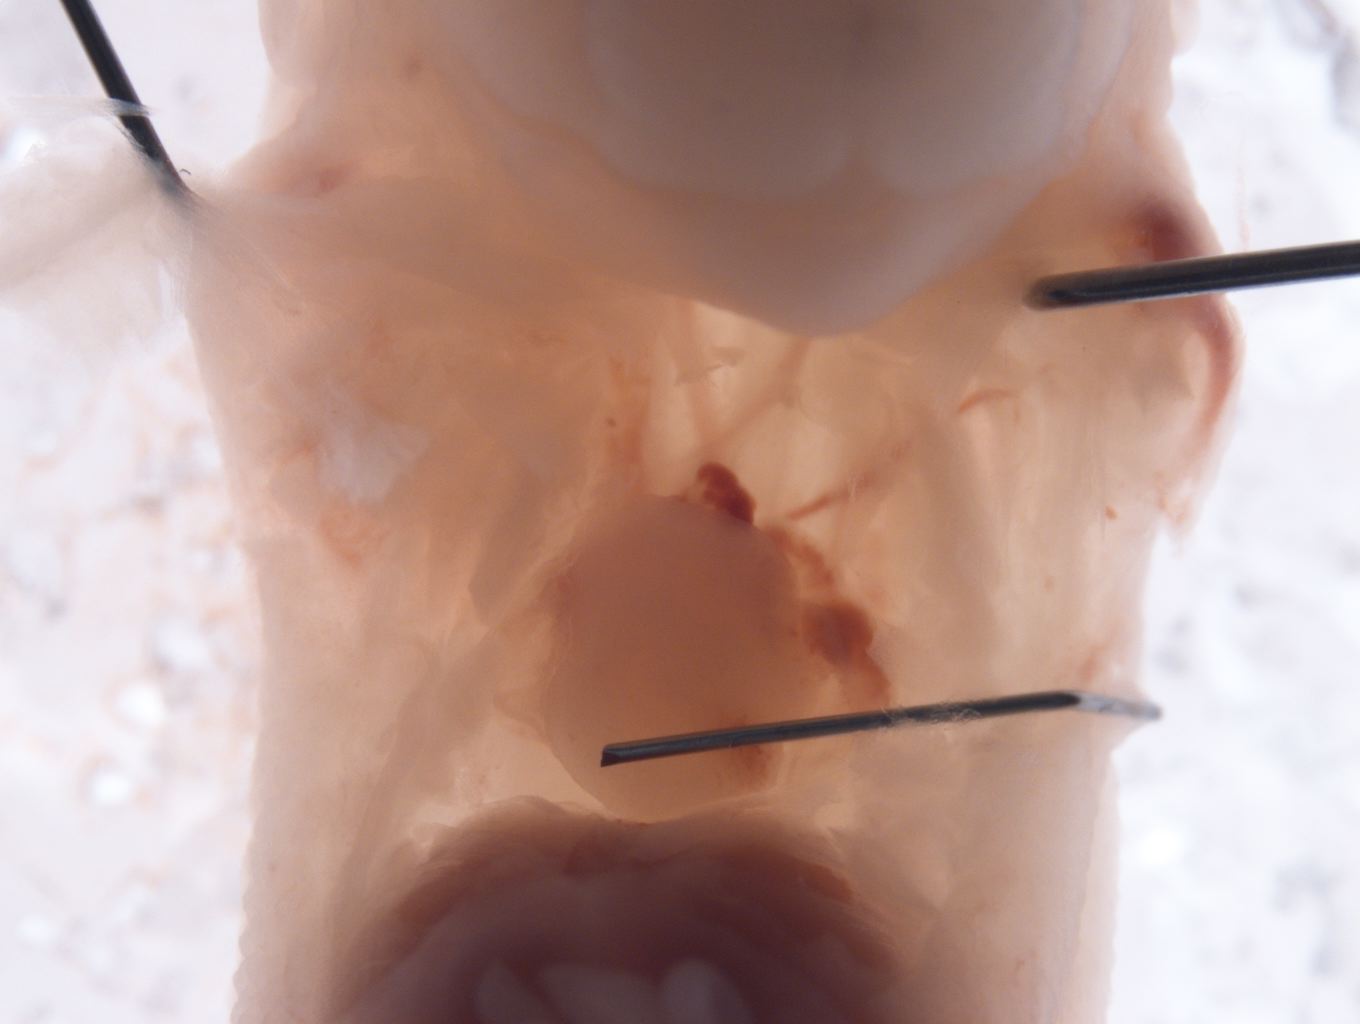

Caption Mutant 2025-005-1 (E14.5) exhibits abnormally positioned heart with superior-inferior positioning of ventricles

Copyright This image is from the Laboratory of Dr. Cecilia Lo, a member of the Cardiovascular Development Consortium (CvDC), Bench to Bassinet (B2B) program of the National Heart Lung and Blood Institute (NHLBI), and is displayed with the permission of the authors. J:175213